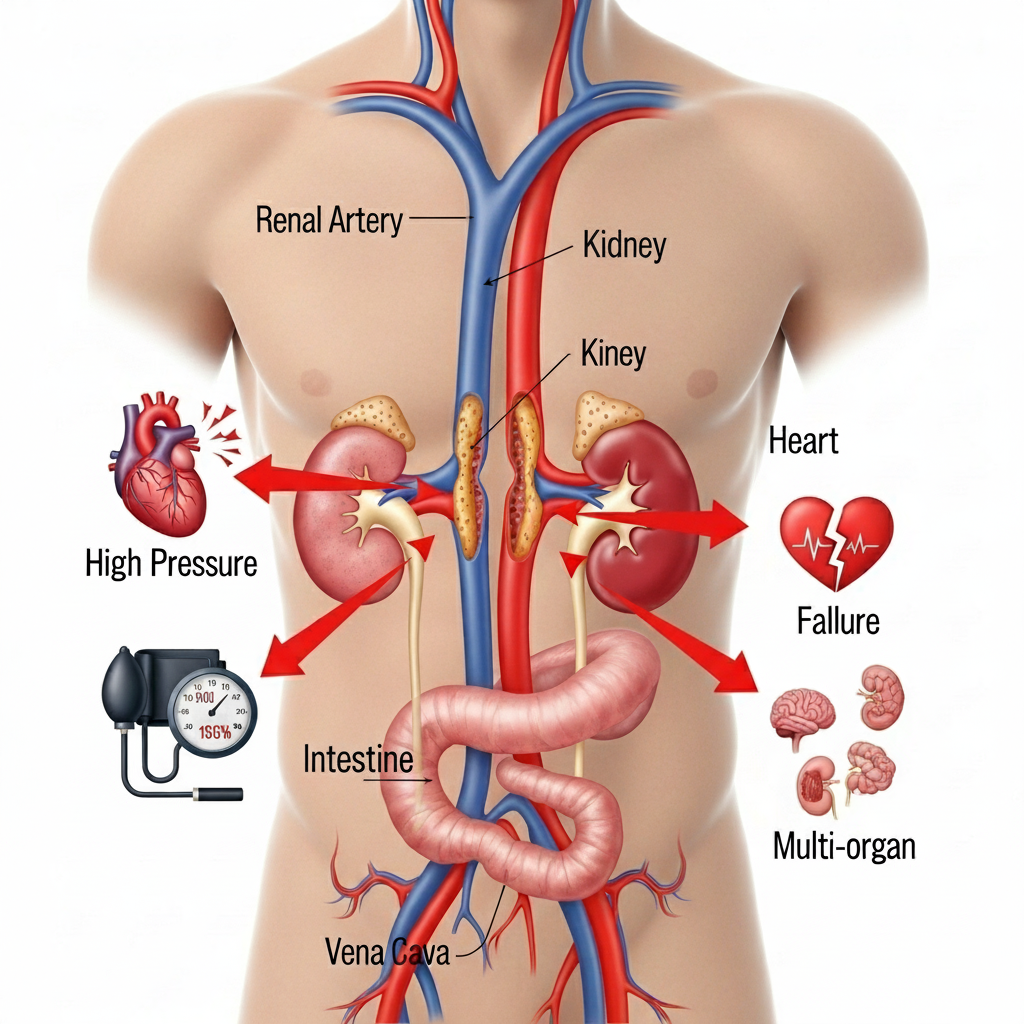

Renal artery stenosis (RAS) is a condition where the arteries that supply blood to your kidneys become narrowed or blocked. This kidney artery narrowing reduces blood flow to the kidneys, leading to high blood pressure and potentially serious complications if left untreated. Understanding this condition is the first step toward effective management and recovery.

Without proper treatment, renal artery stenosis can lead to serious complications:

Progressive loss of kidney function that may require dialysis or transplantation.

Complete loss of kidney function, requiring immediate medical intervention.

Increased risk of heart attack, stroke, and other heart-related conditions.

Fluid accumulation in the lungs due to poor kidney function.

Blood pressure that remains high despite multiple medications.